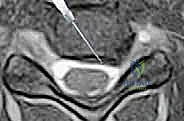

- التصوير بالرنين المغناطيسي (MRI): وهو الفحص الأهم لتحديد موقع الانزلاق الغضروفي بدقة ومدى انضغاط الأعصاب.

الخطوة 3: تحديد مستوى الإصابة بدقة

باستخدام جهاز الأشعة السينية الفلوروسكوبي (Fluoroscopy) داخل غرفة العمليات، يتأكد الدكتور هطيف من الوصول إلى القرص التالف بدقة مليمترية.